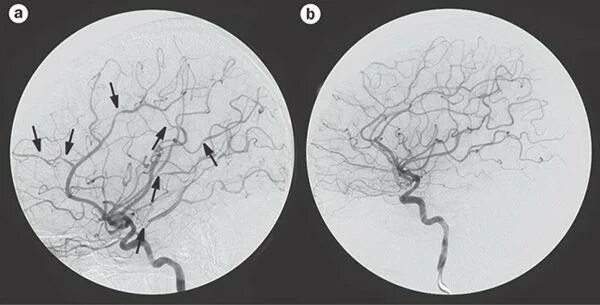

Микроангиопатия головного мозга симптомы